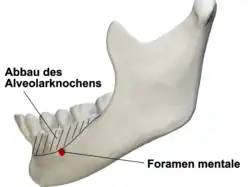

Abbau des Alveolarknochens

Der Abbau des Alveolarknochens beträgt im ersten Jahr nach dem Zahnverlust etwa 0,5 mm im Oberkiefer und 1,2 mm im Unterkiefer. In den Folgejahren beträgt der Abbau 0,1 mm im Oberkiefer und 0,4 mm im Unterkiefer, jeweils pro Jahr.[8] Der schnellere Abbau des Unterkieferknochens resultiert unter anderem daraus, dass die Auflagefläche für eine Prothese nur etwa halb so groß ist, wie die des Oberkiefers. Im Oberkiefer liegt die Prothese auch auf dem Gaumen auf. Dadurch sind die Belastungskräfte, die auf den Unterkiefer wirken, doppelt so groß wie im Oberkiefer. Daraus folgt, dass in der Regel nach etwa 20 Jahren Prothesentragedauer der Alveolarkamm des Unterkiefers vollkommen abgebaut und der Unterkiefer flach geworden ist. Er bietet dann keinen Halt mehr für eine Totalprothese.[2] In solchen Fällen kann durch verschiedene chirurgische Kieferknochenaufbauverfahren der Kiefer wieder rekonstruiert werden. Ein Halt der Prothese kann auch durch Implantate erreicht werden. Damit der Kieferabbau möglichst langsam vonstattengeht, muss die Prothese gut aufliegen. Dies muss durch regelmäßige, in ein- bis zweijährigem Abstand durchgeführte Unterfütterungen („Aufpolstern“) der Prothese erfolgen. Nach etwa fünf Jahren sollte eine Neuanfertigung erfolgen, da der Kunststoff im Laufe der Zeit spröde wird und dadurch die Bruchgefahr der Prothese bei der Kaubelastung steigt.

Im Unterkiefer kann durch den Abbau des Alveolarknochens der Druck der Prothese auf den Nervus mentalis (Kinnnerv), der aus dem Foramen mentale (Kinnloch) austritt, zu einem Taubheitsgefühl der Unterlippe führen. In diesem Fall muss die Prothese in diesem Bereich hohl gelegt werden. Alternativ kann der Nervus mentalis mittels einer chirurgischen Nervverlagerung nach caudal (unten) versetzt werden.[43]